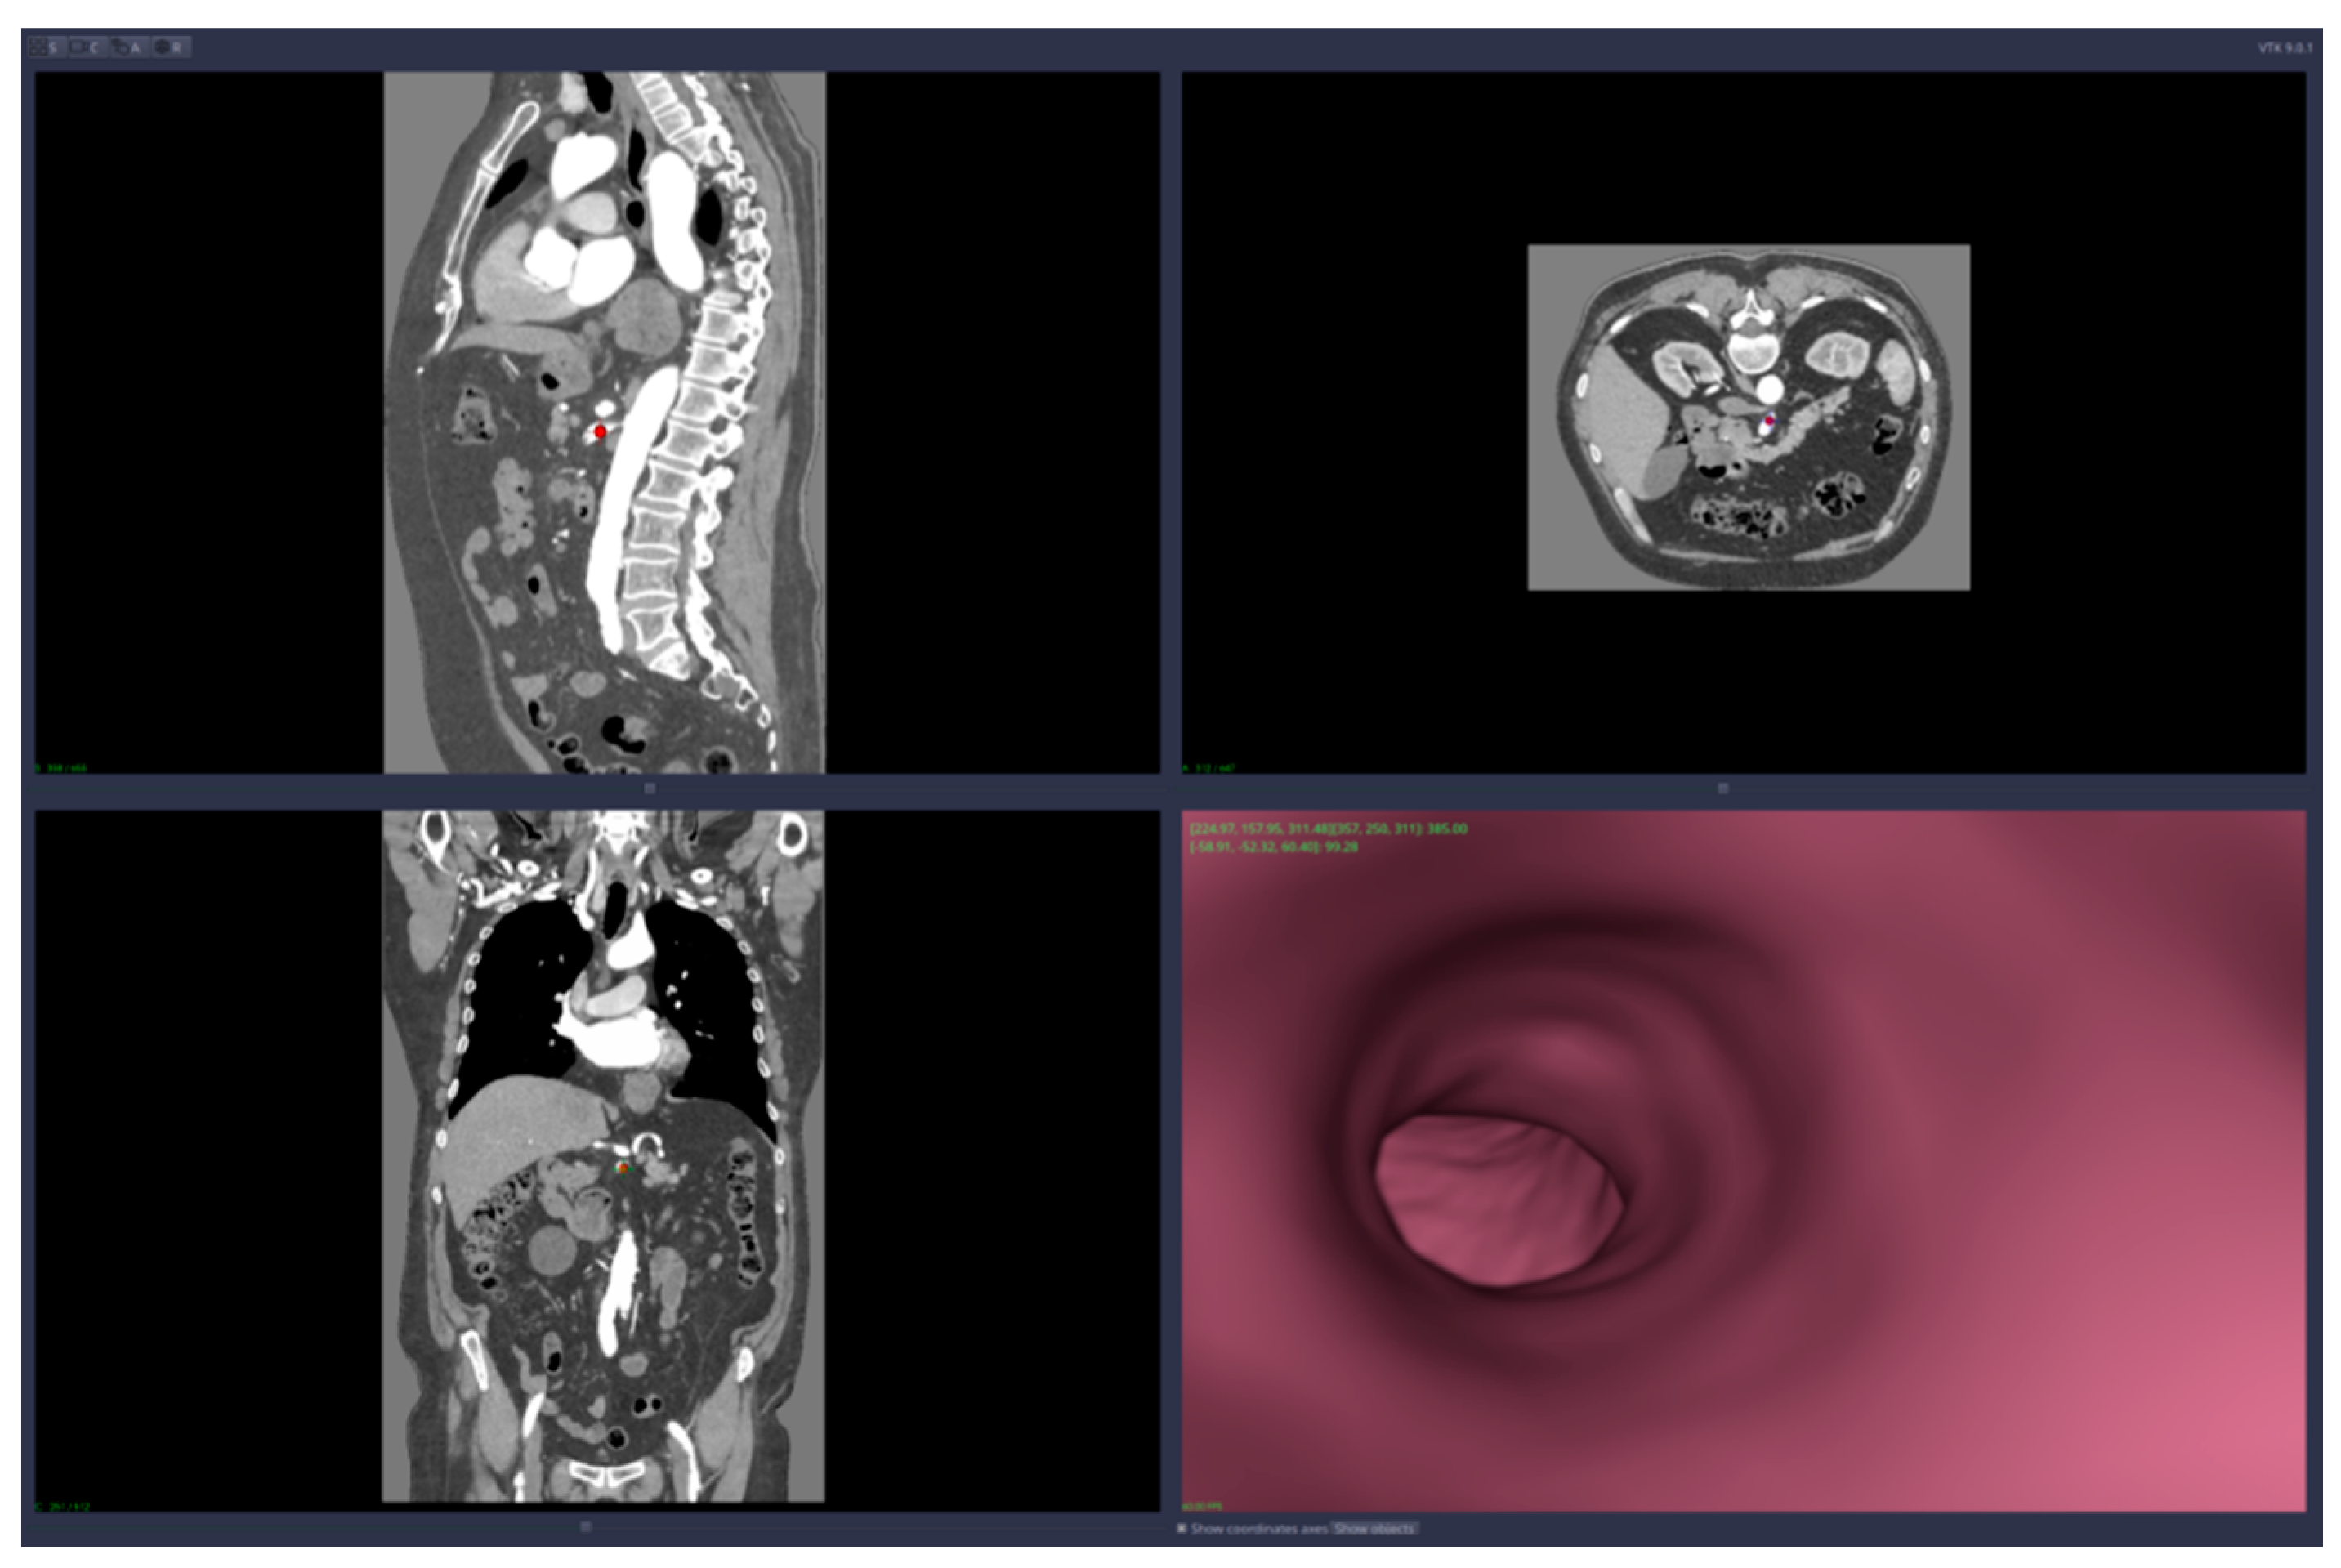

• 3D reconstruction and visualization of arteries (see Figure 1 and Figure 2)

Figure 1. Images of the 3D CT reconstruction and 2D sections.